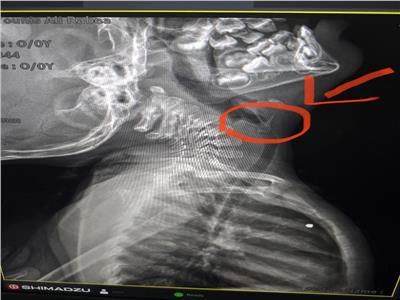

وبعد الفحص الإكلينيكي والأشعة، تبين وجود شوكة سمكة ملتصقة بجدار القصبة الهوائية، فتم تحويل الحالة بشكل عاجل إلى غرفة عمليات الطوارئ بقسم جراحة القلب والصدر.